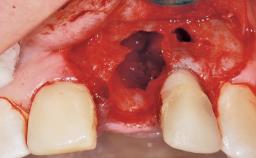

Late Flapless Placement of an Implant in a Maxillary Left Central Incisor Site

A 39-year-old male patient presented with a chief complaint of discomfort and gingival discoloration around his maxillary left central incisor. He was in good general health and was a non-smoker. His past dental history was significant because of the traumatic fracture of tooth 21 in a sporting accident at age 13. Initial dental treatment included endodontic therapy and a full-coverage restoration. The patient became symptomatic 5 years later, when structural failure of the tooth resulted in the dislodgment of the crown. Endodontic retreatment, apical surgery, and post-and-core restoration were performed.

Bone Volume Deficient horizontally, requiring prior grafting

Esthetic Risk High